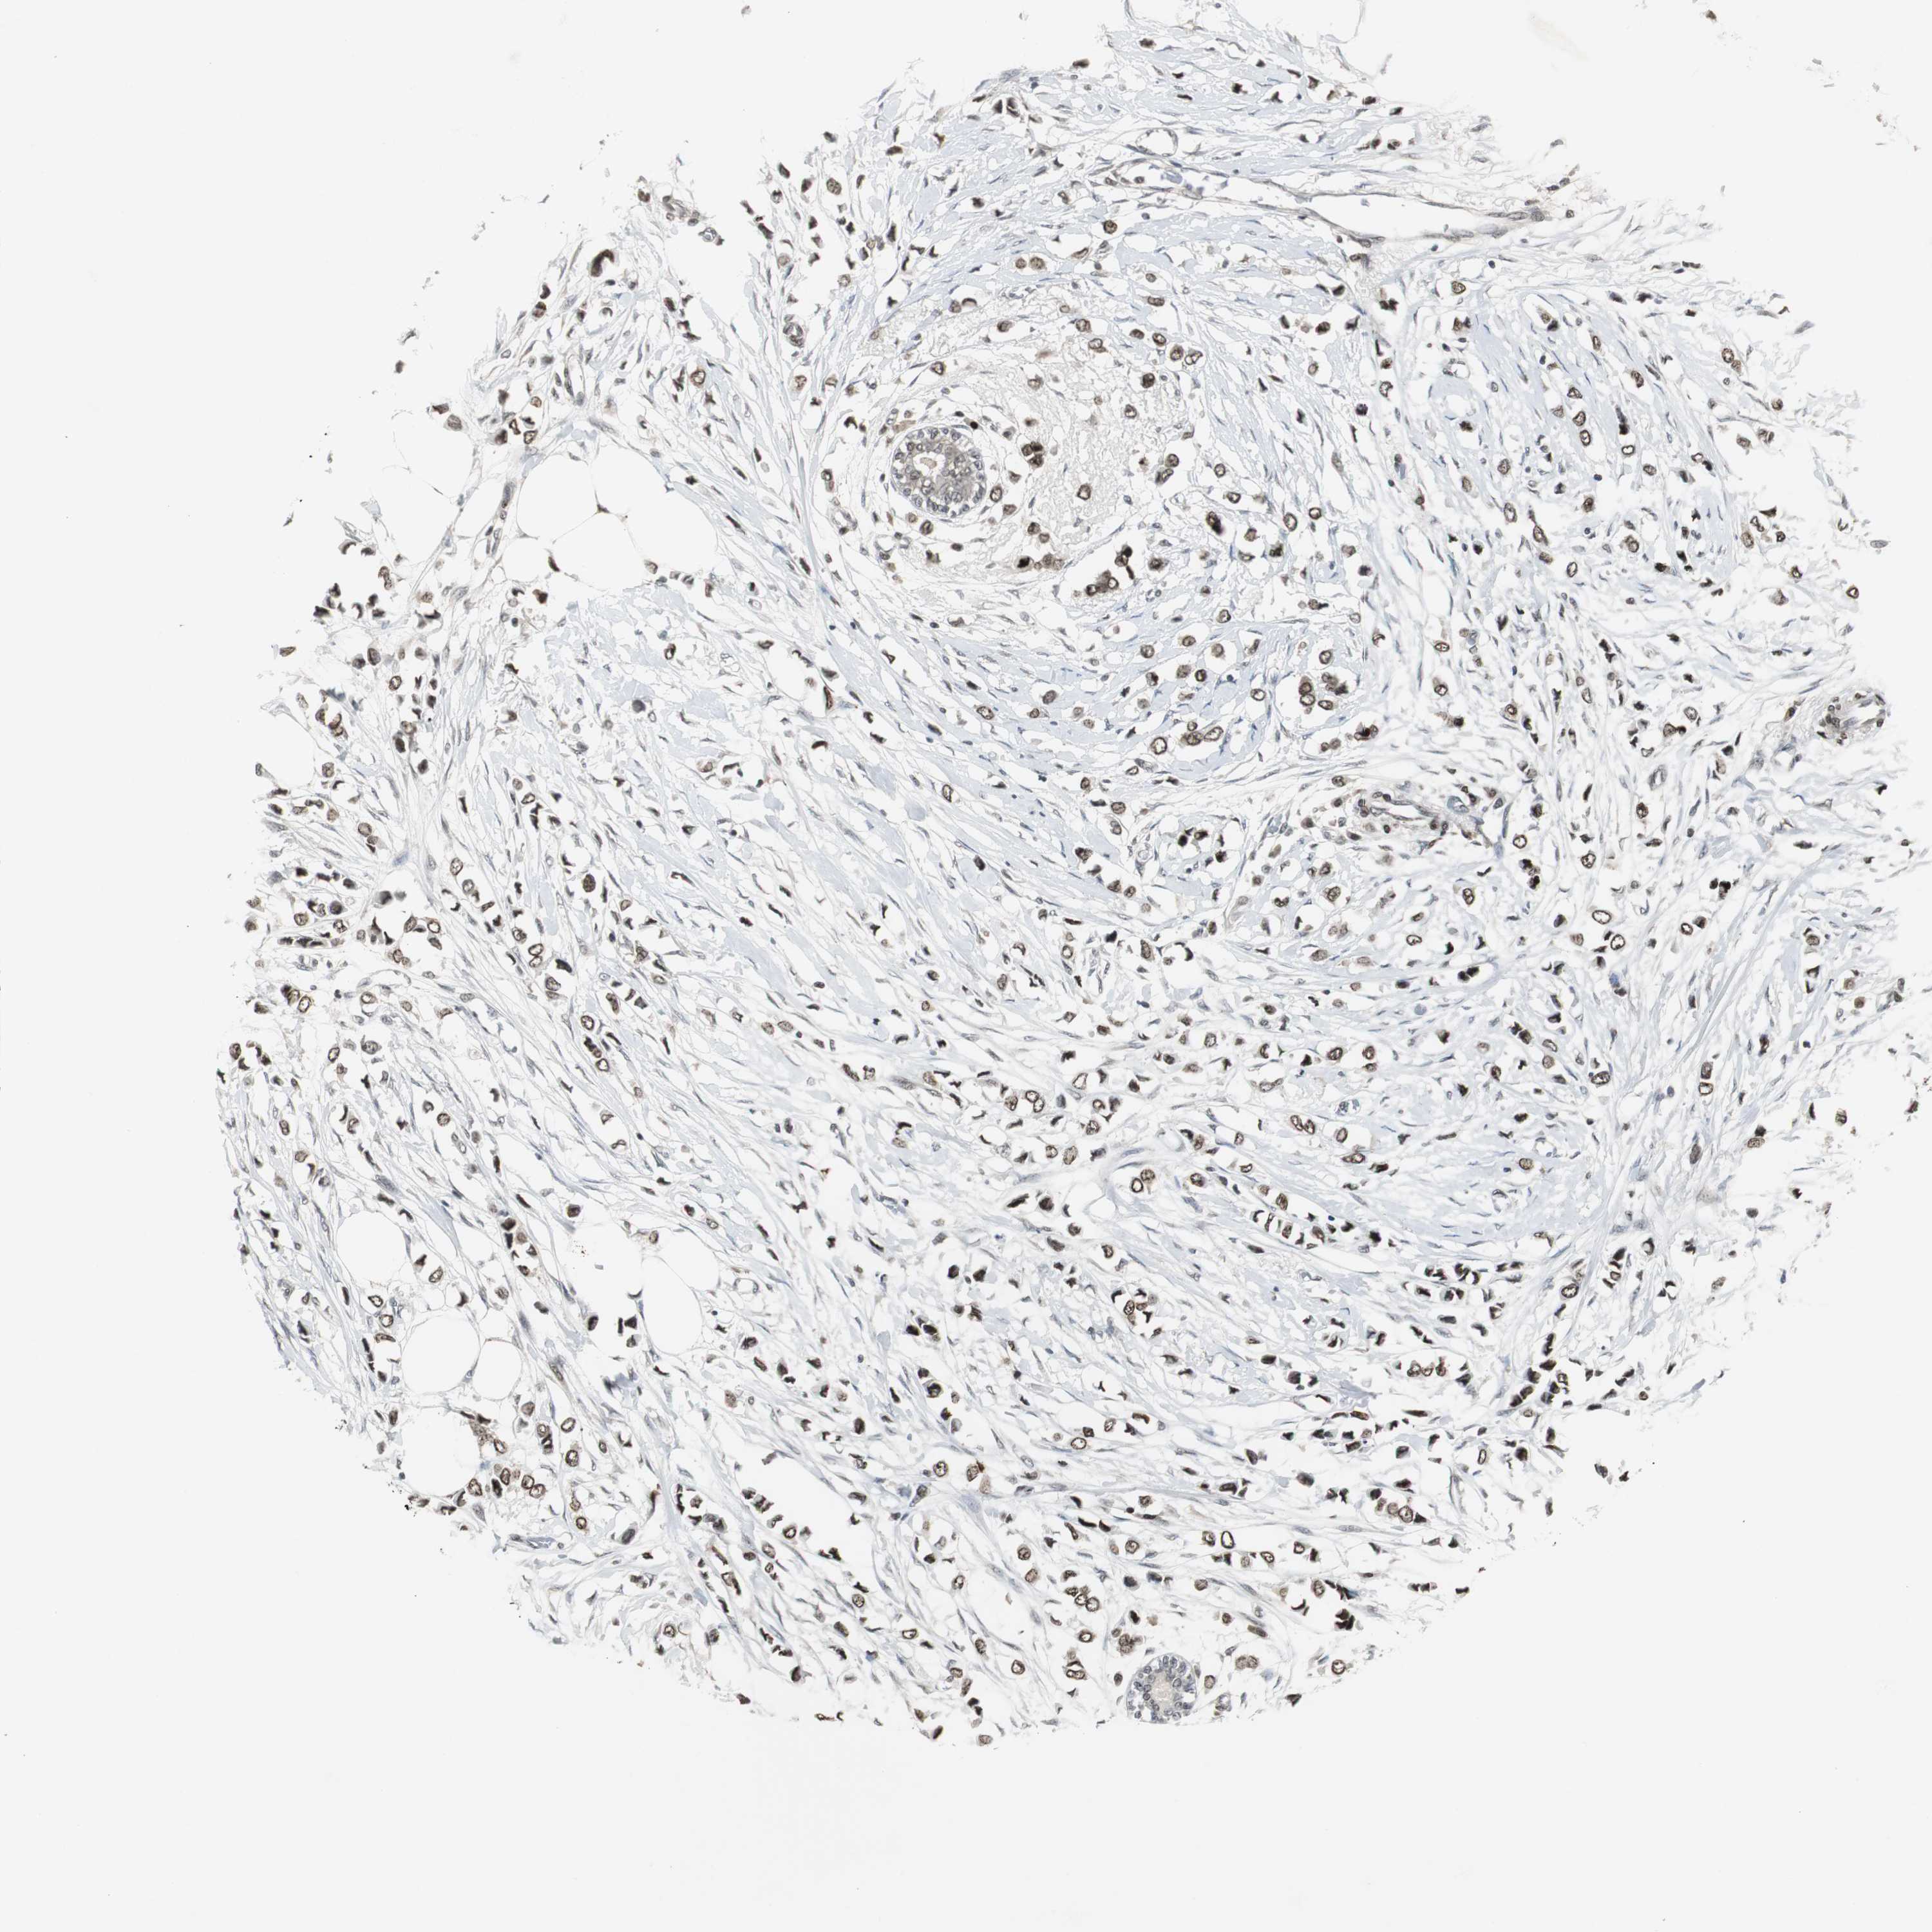

CANCER BREAST CANCER Show tissue menu

BRCA TCGA BRCA VALIDATION PROTEIN EXPRESSION

Breast cancer

Human cancer